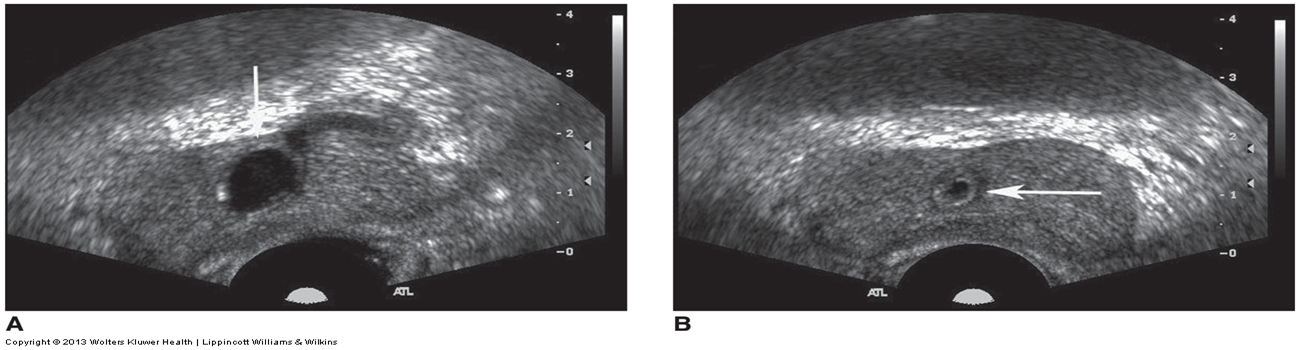

prostatic carcinoma appearance

hypoechoic, peripherally located

can infiltrate and extend beyond capsule